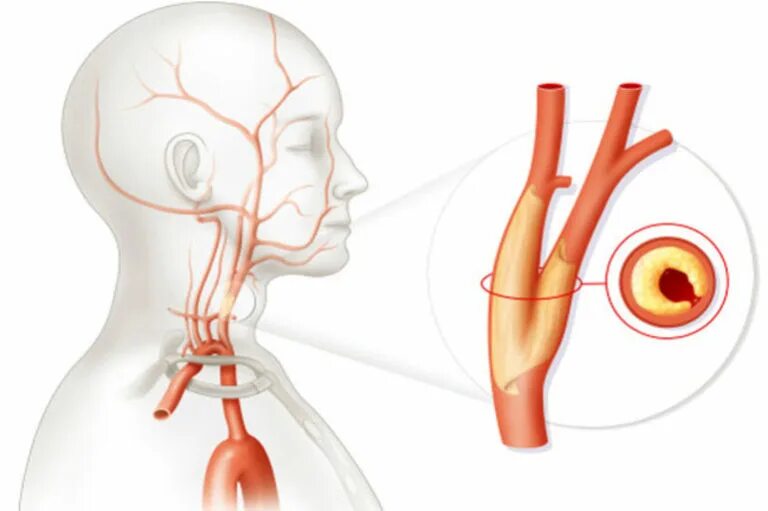

Как лечить стеноз шеи